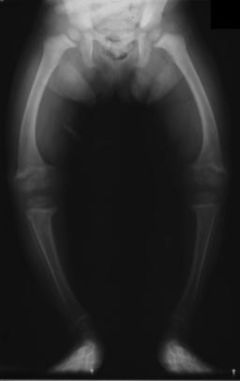

Křivice

Křivice neboli rachitida (rachitis) je onemocnění dětí, vyvolané nedostatkem vitaminu D. Bývá způsobena nedostatečnou výživou, chudou na tento vitamin, ale také nedostatkem slunečního záření, jehož pomocí dovede tělo tvořit z některých látek vitamin.

Tato choroba se projevuje těžkou poruchou tvorby kostí - kosti měknou, převažuje chrupavčitá hmota. Zatímco ve zdravé kostní tkáni je chrupavčité složky asi 30%, v rachitické kosti až 70%. Ubývá značně fosforečných solí, kdežto obsah vápenatých solí se celkem nemění. Kostní změny mají za následek, že dochází k poruchám ve tvaru kostí. U kojence měknou kosti lebeční, zvláště týlní. Zuby rostou nepravidelně a jsou na kousacích plochách zoubkované, tvrdé patro je vysoko klenuté. Na žebrech je přechod části chrupavčité v kostní značně ztluštělý a tvoří tzv. rachitický růženec. I na ostatních kostech jsou hranice chrupavky a kosti zduřelé, kosti dolních končetin se ohýbají, dítě přestává chodit. Také obratle se hroutí a tím vznikají různé zkřiveniny páteře.